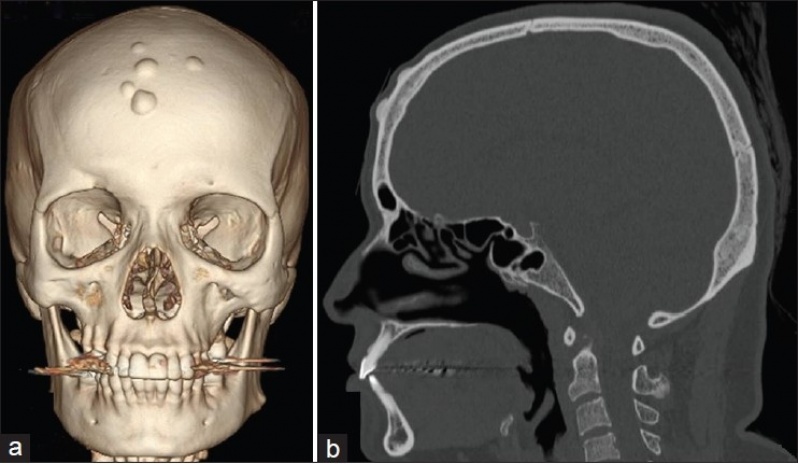

Com um exame de tomografia é possível captar imagens em tons de cinza de determinadas partes do corpo ou de algum órgão do paciente. A preparação para realizar o exame de tomografia é simples e consta apenas de cuidados anti-alérgicos.